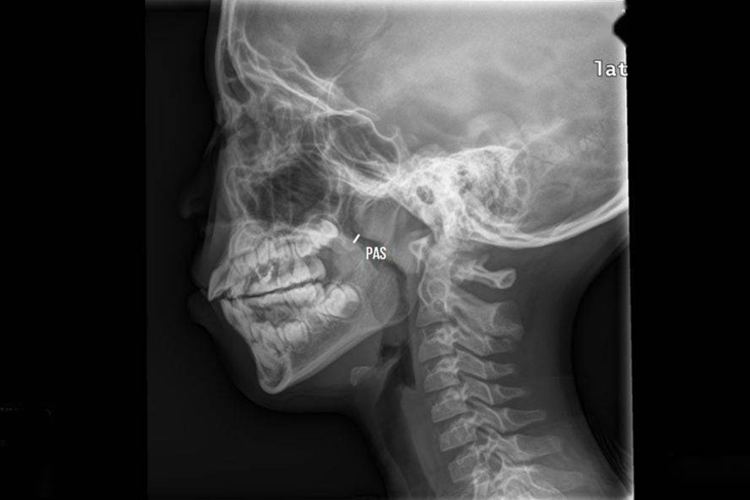

腺样体肥大通过拍摄鼻咽部侧位X线,测量腺样体的厚度和测量鼻咽腔的宽度,然后计算两者的比值可进行判定。比值0.5-0.6为正常;0.61到0.70为中度肥大;0.71以上为病理性肥大;0.8以上为显著肥大。

同时,需结合患者的临床表现,如鼻塞、张口呼吸、打鼾、听力减退、耳鸣等,来进行综合判断。